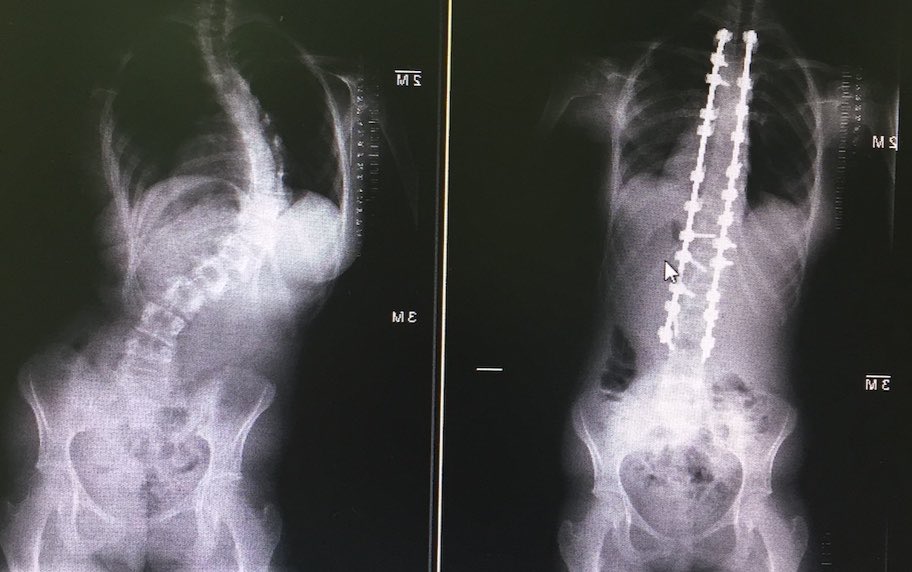

بتوفيق الله، اليوم نشر بحثنا في المجلة الرسمية لجمعية أبحاث الجنف المرموقة، تتناول الدراسة الطعم العظمي في عمليات الجنف وهي مراجعة منهجية وتحليل لخبرات المراكز الاخرى.

بفضل الله، اليوم تم نشر بحثنا في المجلة الرسمية لجمعية العمود الفقري الأوروبية، الرائدة في هذا التخصص.